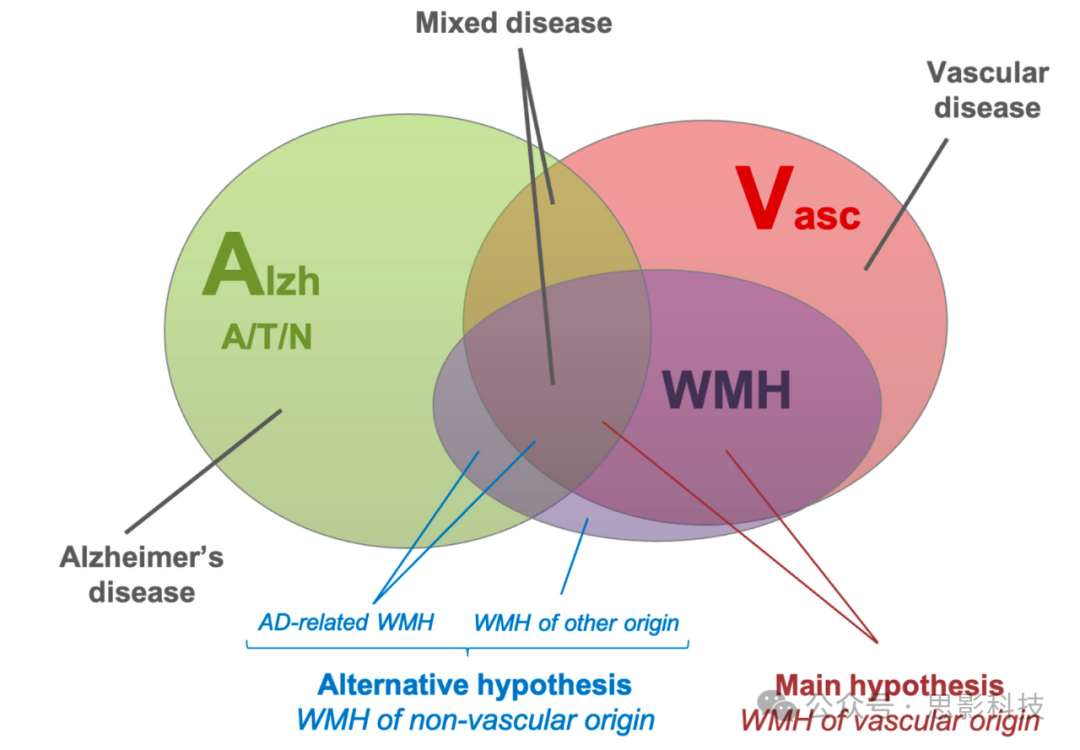

3 一种替代假设:与 AD 相关的 WMH 病灶

一种较少被关注的假设认为,WMH 并非都由缺血性改变所导致;换言之,WMH 不一定全部源于血管因素。因此,除“血管性”WMH 外,在阿尔茨海默病(AD)中所观察到的一部分 WMH 也可能是由 AD 病理过程引起的,例如源于 AD 相关的神经变性或其他机制(见图 2)。

图 2 AD 中白质高信号(WMH)的异质性

该维恩图示意了 AD、血管疾病与 WMH 三者间的关系,凸显了 AD 中 WMH 可能的病因多样性。WMH 主要被视为血管起源(主流假设),或同时包含血管性与非血管性成分(包括继发于 AD 神经变性的 AD 相关 WMH,替代假设)。图中绿色圆圈表示阿尔茨海默病病理(Alzh),其生物学定义通常以 A/T/N(三大标志:淀粉样蛋白/tau/神经变性)为核心;红色圆圈表示血管性病理。

缩写:AD, Alzheimer’s disease;Alzh, Alzheimer’s pathology(绿色);A/T/N, amyloid/tau/neurodegeneration(与 AD 生物学定义相关);WMH, white matter hyperintensities;Vasc, vascular pathology(红色)。